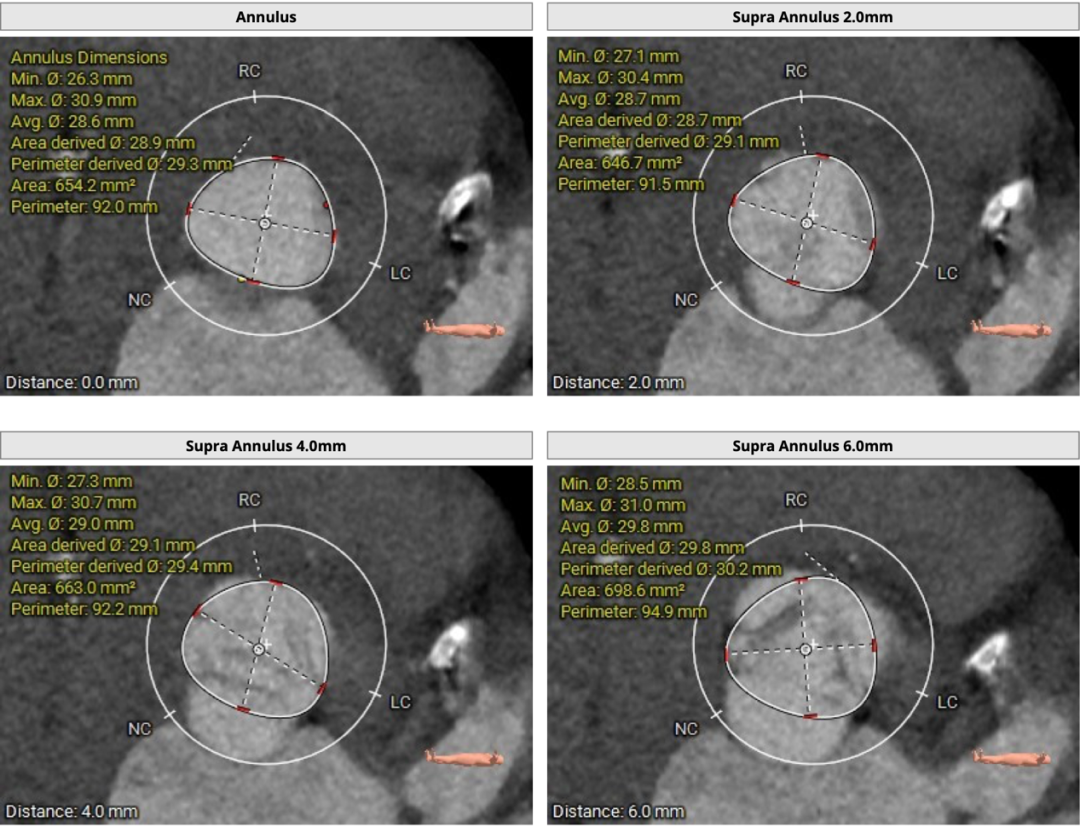

CT分析

患者主动脉瓣三叶式,瓣叶基本等大,瓣叶增厚,瓣叶未见明显钙化。主动脉瓣环周长折算直径约29.3mm:

主动脉根部径线:

双侧冠脉开口高度可LCA:14.5mm, RCA:22.9mm;右冠轻度钙化,左冠及分支中度钙化: